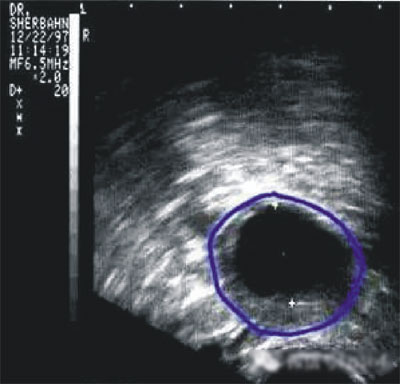

陰道B型超聲動(dòng)態(tài)監(jiān)測(cè)卵泡的發(fā)育及排卵,是監(jiān)測(cè)排卵最準(zhǔn)確可靠的方法。通過陰道B超檢查可以了解子宮及雙側(cè)附件(卵巢和輸卵管)區(qū)的基本情況,測(cè)定卵巢內(nèi)的竇卵泡計(jì)數(shù),評(píng)估卵巢儲(chǔ)備功能,動(dòng)態(tài)監(jiān)測(cè)排卵。